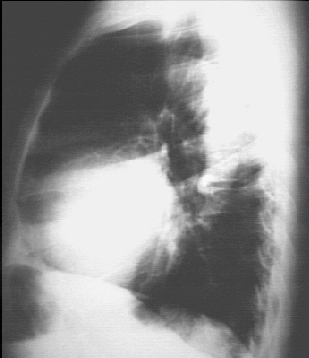

The lateral view shows left ventricular enlargement, as evidenced by posterior displacement of the left ventricular shadow.